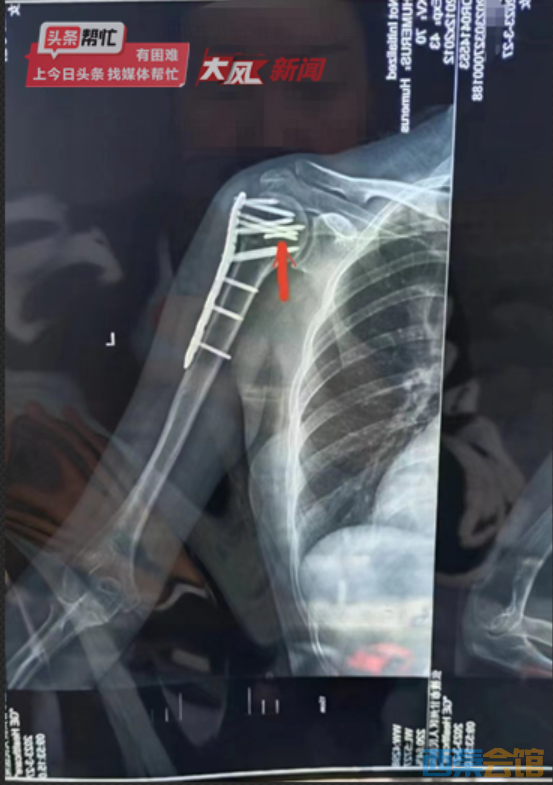

杨女士的左肩手术部位CT 片子显示,肩膀下方一根呈螺旋状的细棒状物体清晰可见

多方咨询:有专家建议保留钻头,称取出或会伤及胳膊神经杨女士的左肩手术部位CT 片子显示,肩膀下方一点肱骨明显有钢板固定,但一根呈螺旋状的细棒状物体也清晰可见,薛先生表示,那就是当初手术时断在骨头中的钻头。